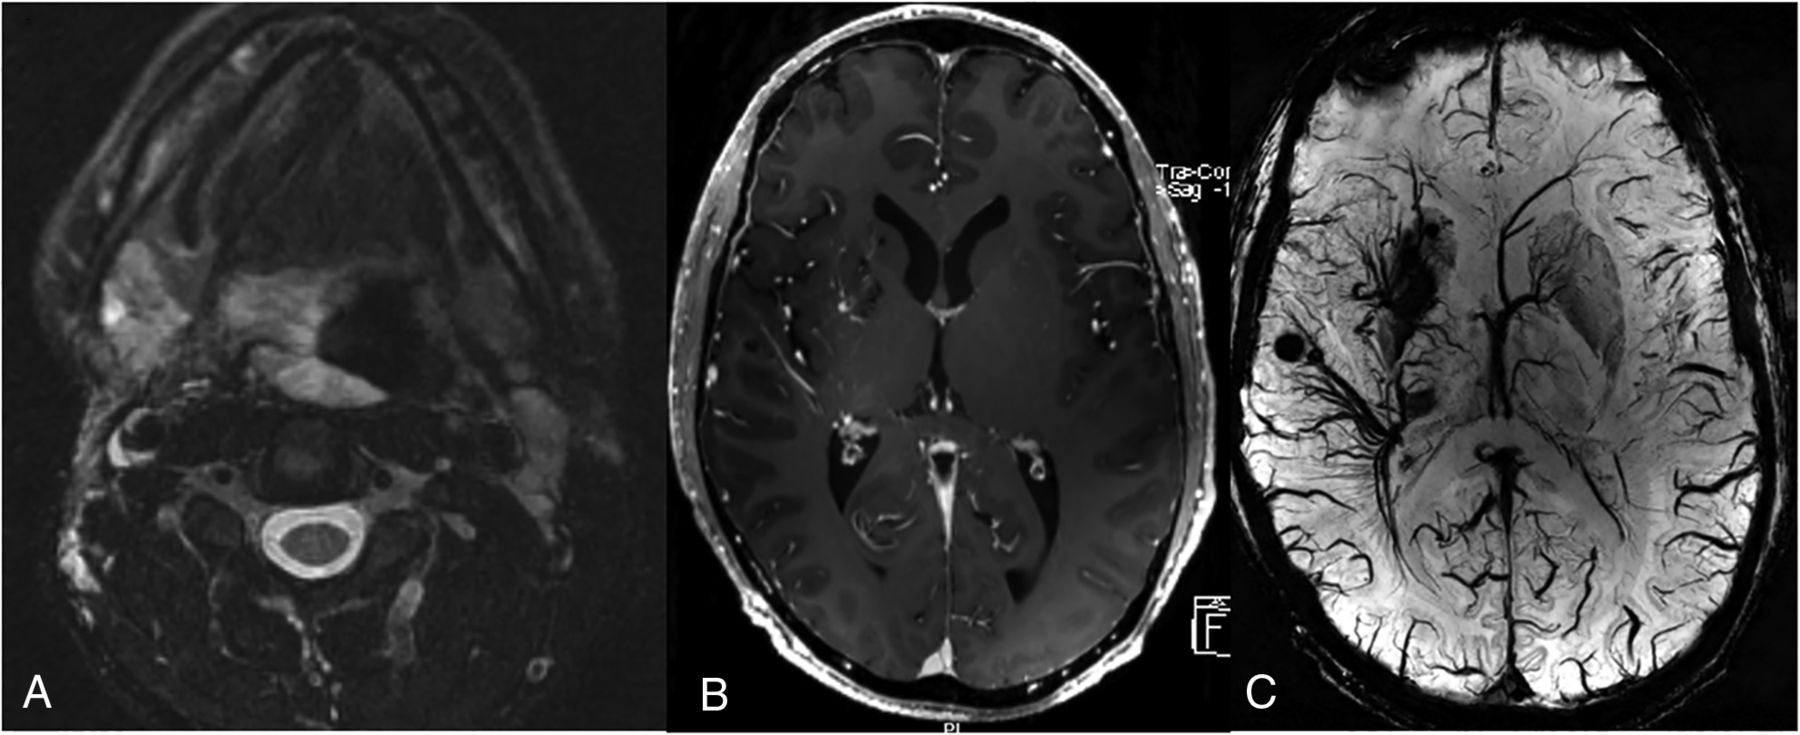

A 38-year-old man with extensive airway malformation. A, T2 FS MR imaging shows an extensive venous malformation involving the airway and tongue base. B, Axial postcontrast MR imaging shows extensive DVAs of the right frontal lobe, basal ganglia, and temporal lobe. C, 7T SWI shows the extensive DVAs and multiple cavernomas in the radicles of the DVAs.